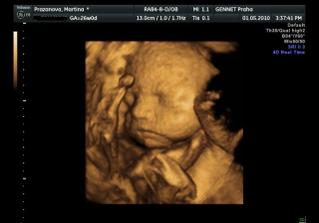

Určitě dám sem vědět i s aktuální fotečkou. Jména mám v pase. A 1.května jdeme na 4D UTZ, tak se moc těšíme 🙂

Letí to jak blázen, vždyť to znáš 🙂. Zatím nevíme nic, ale zítra jdeme na velký genetický UTZ, tak snad tam prcek nebude sedět v tureckém sedě jako minule 🙂))